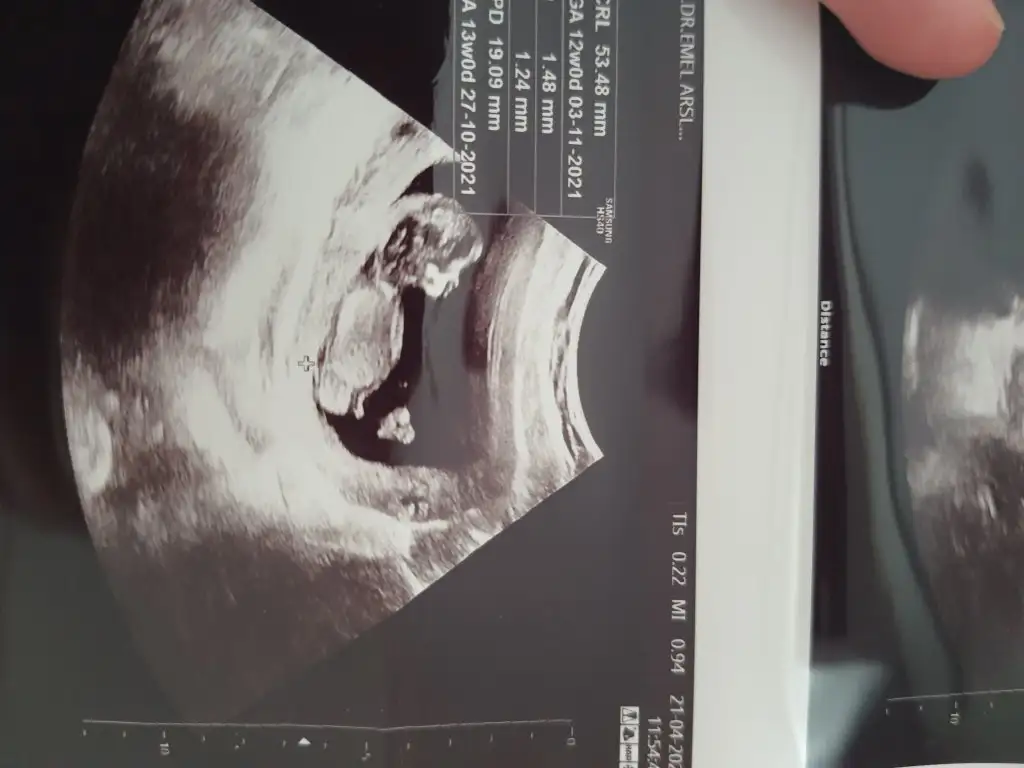

Ikra meyra Ikra meyra rica etsem benimkine de bakabilir misiniz 14.hafta 11. Haftada başka doktor kız gibi demişti 14. Hafta da gittiğim doktor da erkek dedi siz görebiliyor musunuz acaba🙈

anladığımdan değil ama kafatası teorisine çok bakmıştım ona göre kız gibi geldi.. bir de diğer usg de genital bölge çatallı.. ☺️

Doktor 11. Haftada kız gibi dedi ona alıştım başka doktor da 14. Hafta erkek dedi ben çok anlamıyorum ama belki yine değişir diye bekliyorum, 20 sinde kontrolüm var o zamana kadar netleşir belki 😊